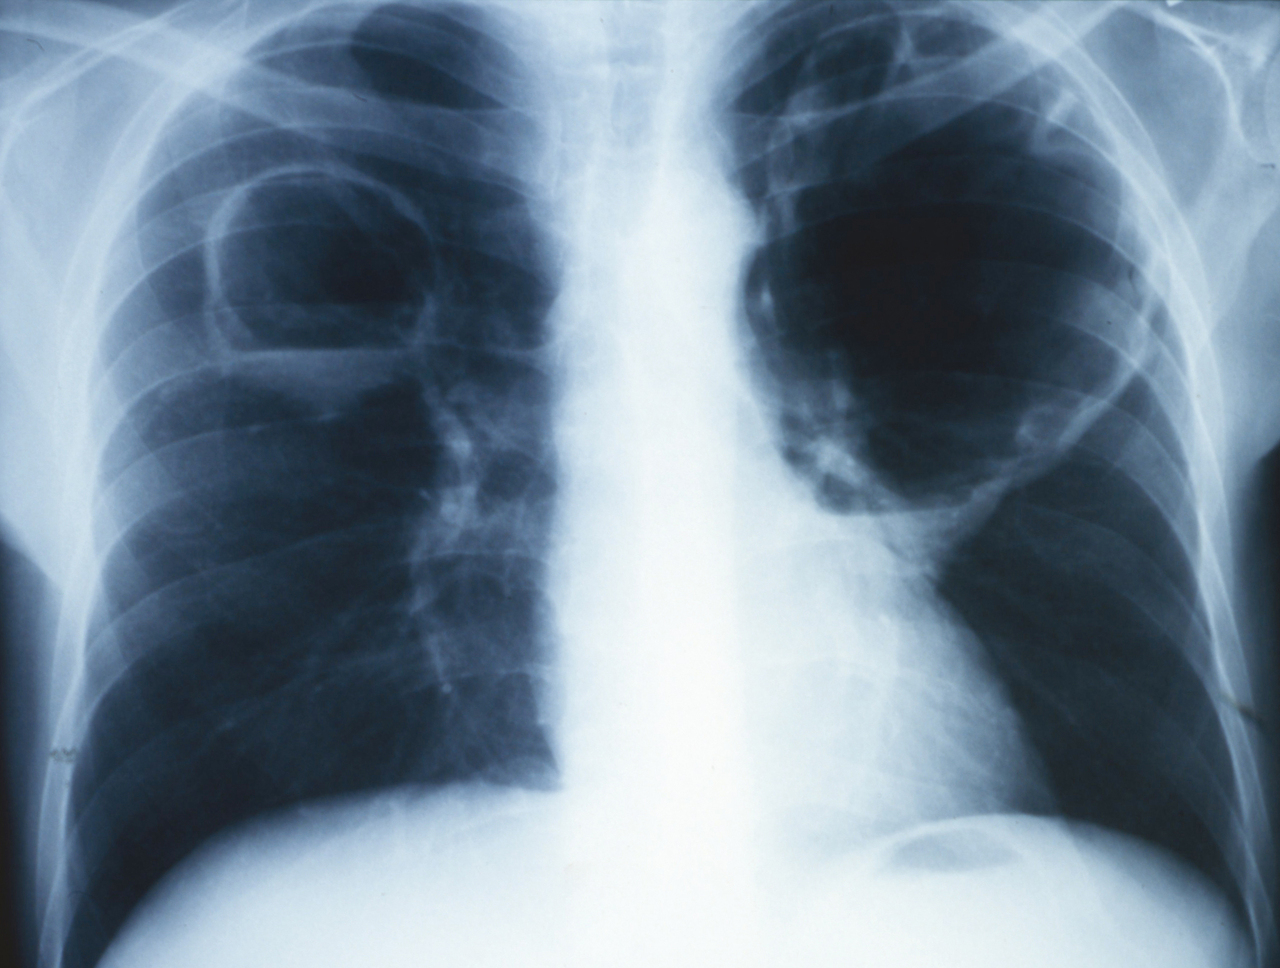

Quel est votre diagnostic ?

Il s’agit d’abcès du poumon. Les abcès du poumon, uniques, ou multiples comme ici, produisent des opacités excavées à parois épaisses, localisées dans 70 % des cas dans les zones postérieures. Les agents infectieux en cause sont le plus souvent les bacilles à Gram négatif et les streptocoques d'origine bucco-dentaire chez l’adulte, et le staphylocoque chez l’enfant. Le germe en cause ici est le staphylocoque. Les pneumopathies à Staphylococcus aureus sont rares et correspondent à moins de 5 % des pneumopathies communautaires. Elles surviennent souvent dans un contexte post-grippal en raison de l’atteinte de l'épithélium respiratoire qui favorise l’infection par S. aureus.